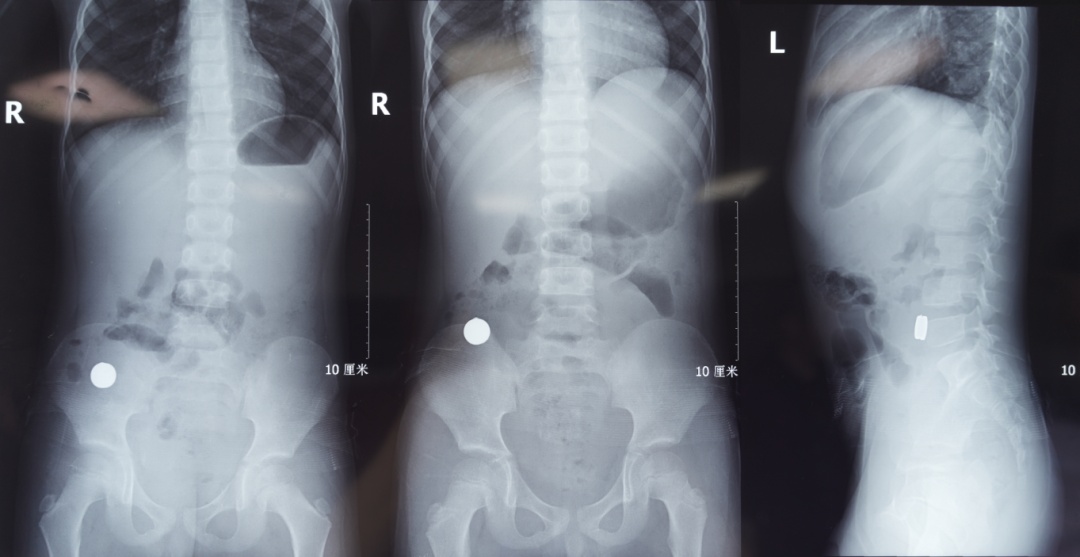

“腹腔镜进去后,发现第一枚磁铁是在升结肠的位置,第二枚磁铁在距离小肠的末端——回肠大概五六十厘米的地方,两枚磁铁紧紧地吸在一起,中间还夹住了一块小肠。”主刀医生普外新生儿外科袁亮主治医师说,取下磁铁后,发现四处肠穿孔,只有将坏死的肠管进行切除后缝合。